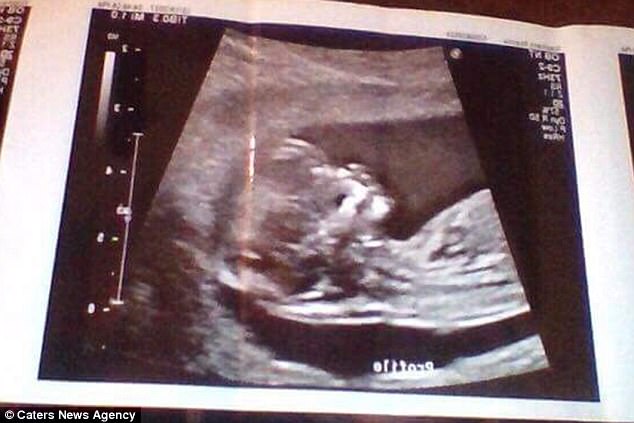

The 18-year-old is expecting her son in April. But she is so slim, strangers have accused her of faking her pregnancy.

She said: ‘My baby is growing the perfect amount every month as it’s measured, just like everyone else’s, so it’s absolutely nothing to do with mine or the baby’s health.’